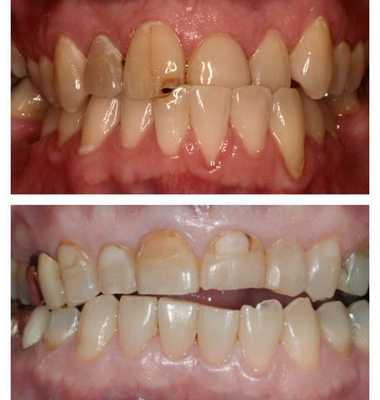

Глубокий прикус, скученность, сужение зубных рядов, эффект Попова Годона, смещение центральной линии, генерализованный пародонтит, протрузия, адентия

Глубокое резцовое перекрытие, сужение обоих зубных рядов, ротация и девиация нижней челюсти, смещение центральной линии

Начальная степень глубокого прикуса выражается образованием небольших эстетических дефектов передних зубов - трещинки, мелкие сколы эмали.

Глубокий прикус средней тяжести - интенсивное стирание эмали на внутренней стороне верхних зубов и на внешней стороне зубов нижней челюсти.